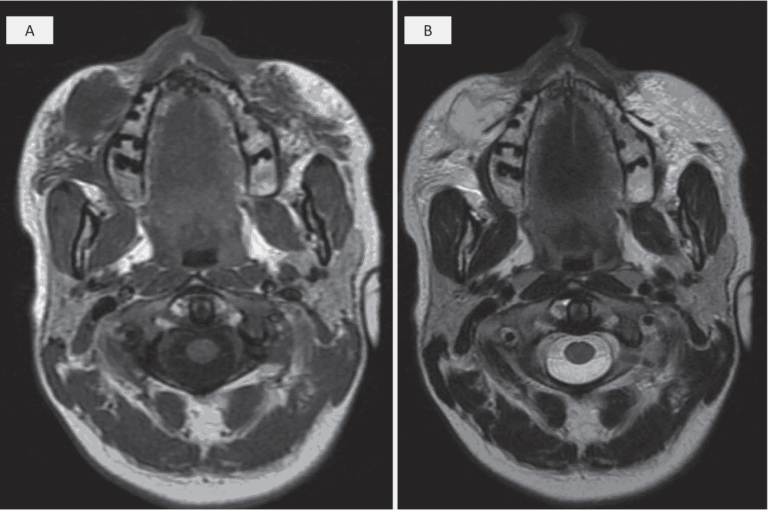

Treating facial overfilled syndrome with impaired facial expression—Presenting clinical experience with ultrasound imaging

- Schelke L, Harris S, Cartier H,

Cotofana S, et al;

J Cosmet Dermatol

Dec 2023

Anatomy Behind Facial Overfilled Syndrome - The Transverse Facial Septum

- Cotofana S, Gotkin R,

Frank K, Et Al;

Dermatologic Surgery

Aug 2020